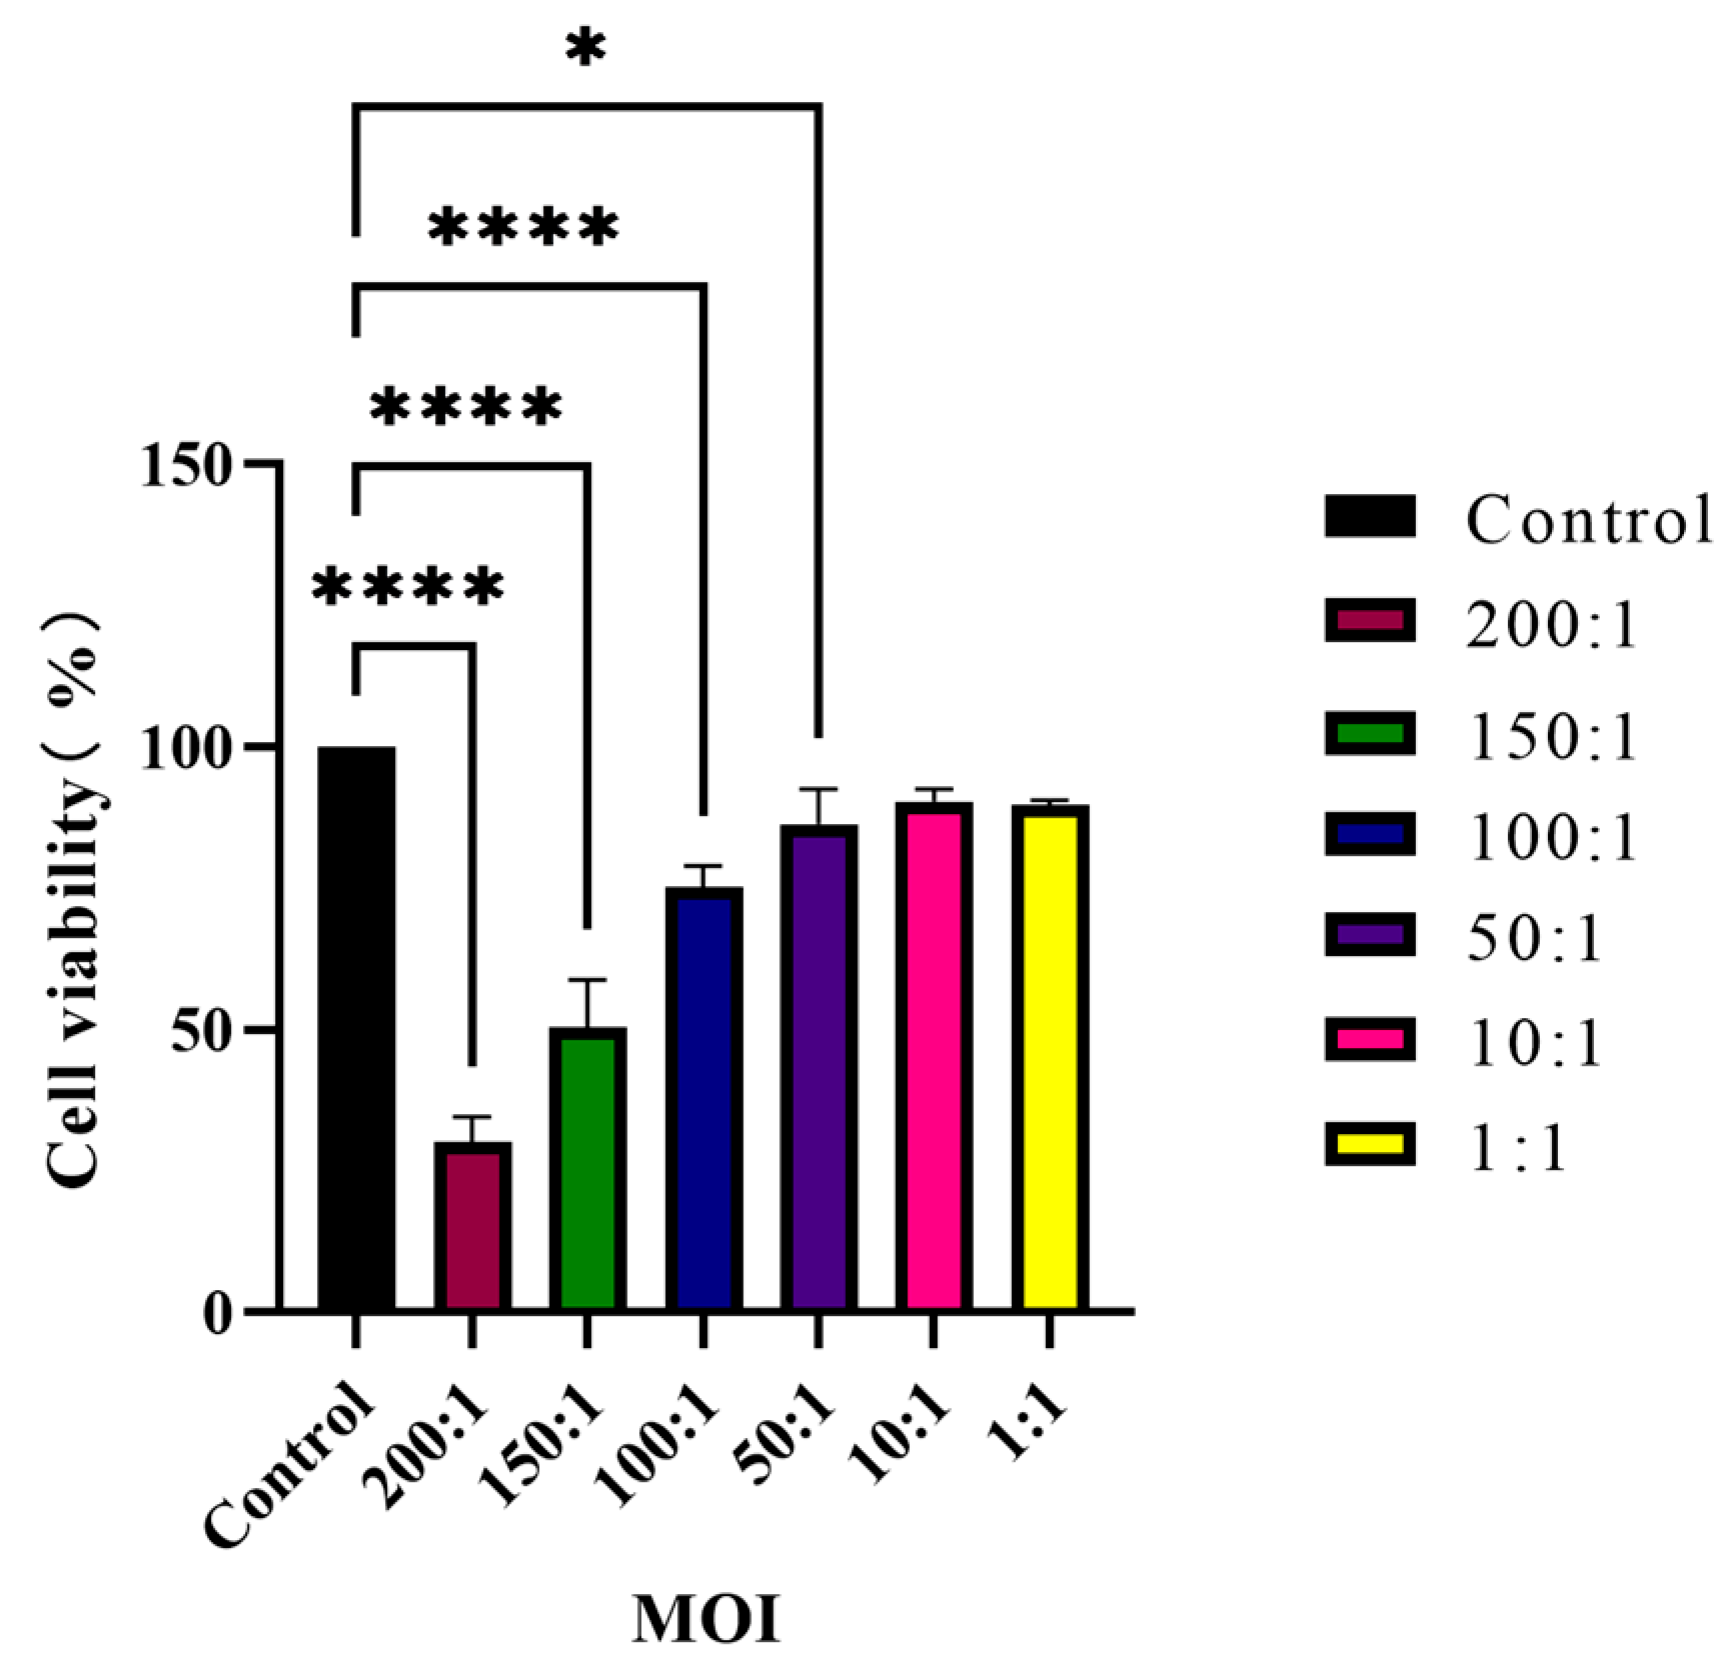

2.9. Host Cell Viability Assay

HaCaT cells seeded in 96-well plates were co-cultured with

C. acnes IA

1 (CICC 10864) at MOIs of 200:1, 150:1, 100:1, 50:1, 10:1, and 1:1. Meanwhile, the corresponding series of bacterial suspension concentrations cultured without keratinocytes served as blank controls, whereas keratinocytes cultured without bacteria were defined as negative controls. After 24 h, cell viability was determined by using cell-counting kit 8 (CCK-8, Beyotime Biotechnology). Firstly, the culture medium was removed by aspiration and centrifugated at 13,000×

g for 5 min. The supernatant was then collected and stored at −80 °C for further experimental use. Next, a CCK-8-containing medium was added to each well and incubated for 1 h in a CO

2 incubator at 37 °C. The absorbance value was measured on a Spark Multimode Microplate Reader (Tecan Trading AG) with a test wavelength of 450 nm and a reference wavelength of 630 nm.

AS: The absorbance of keratinocytes co-cultured with bacteria cells.

Anc: The absorbance of keratinocytes cultured without bacteria cells.

Abc: The absorbance of bacteria cells cultured without keratinocytes.

All the statistical analyses were performed using GraphPad Prism Version 9.0.0 (GraphPad Software Inc., San Diego, CA, USA). Data were expressed as means ± standard deviation (SD) of three biological replicates or three independent experiments. Paired t-test or ordinary one-way analysis of variance (ANOVA) with Dunnett’s multiple comparisons test was used to identify significant variations. p < 0.05 was considered to indicate a statistically significant difference.